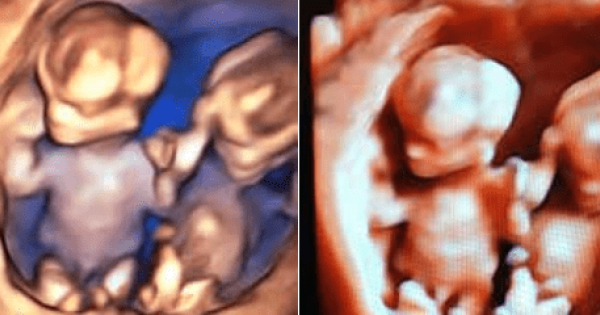

Sempre più spesso, i servizi erogati per la tutela del benessere e della salute della Donna e del Bambino rappresentano un indicatore di qualità dell’intera offerta sanitaria erogata alla comunità. Nell’ottica di tale “concezione moderna di salute”, la medicina materno-fetale non può non ricoprire un ruolo prioritario, essendo l’unico momento della vita di una donna in cui “è possibile definire il benessere del paziente presente (mamma) e del paziente futuro (feto)”. Per molteplici aspetti socio-economici, la maternità ha subito negli ultimi anni notevoli cambiamenti, in primis fra tutti l’essersi spostata come evento nella “medio-tarda” età fertile. Tale tendenza, che non potrà che continuare, induce nella coppia la pianificazione di un numero sempre inferiore di figli, spesso ricorrendo a tecniche di procreazione medicalmente assistita (e quando necessario anche con utilizzo di gameti eterologhi), aumenta potenzialmente i rischi materni e fetali (gravidanza a rischio), ma al contempo incrementa esponenzialmente il desiderio/necessità di predizione di benessere. Ecco che diventa “normale” la richiesta della coppia del “massimo” in termini di aspettativa di salute, di predizione del rischio e di diagnosi rapide, veloci, esaustive ed accurate. Il Poliambulatorio Affidea Delta Medica in collaborazione con il Dr. Gizzo Salvatore - Specialista in Ginecologica ed Ostetricia – offe già da alcuni anni la possibilità alla donna incinta di soddisfare, con minimo tempo di attesa e costi contenuti, il desiderio di predizione di benessere suo del suo futuro nascituro. Ecco che, oltre alla routinaria visita ostetrica, è possibile nella stessa occasione effettuare l’ecografia ostetrica ad hoc per qualsiasi epoca gestazionale. L’ecografia ostetrica, oltra al battito cardiaco fetale e alla diagnosi di presentazione permette di valutare il rischio di patologie cromosomiche già nel primo trimestre di gravidanza (ecografia genetica del primo trimestre). L’ecografia del secondo trimestre, meglio conosciuta come ecografia morfologica, è il massimo concentrato delle potenzialità dello studio ecografico: questa è l’epoca gestazionale in cui si ha il miglior rapporto tra le dimensioni del feto stesso e la risoluzione dell’apparecchio, al fine di eseguire un’analisi morfostrutturale. Si possono investigare estensivamente parametri della crescita e del benessere fetale, implementando lo studio con la visualizzazione e valutazione della vascolarizzazione fetale ed uterina. Nelle successive settimane di gravidanza è possibile monitorare il benessere fetale e di realizzare uno studio particolareggiato della struttura, valutarne l’accrescimento, con la possibilità attraverso complesse formule matematiche di determinare una stima del peso e della lunghezza fetale al momento stesso e con buona approssimazione al parto. Le pazienti che si rivolgono al Poliambulatorio Affidea Delta Medica potranno usufruire inoltre di test di screening genetici non invasivi di 1° livello (Ultrascreen o meglio conosciuto come Bi-Test) nonché del sempre più diffuso e richiesto “Test del Dna Fetale circolante [cfDNA]”. I test basati sul cfDNA, in quanto analisi del DNA, sono test genetici a tutti gli effetti, potendo eseguire uno screening cromosomico ad elevata performance (altra sensibilità ed alta specificità) sia per le cromosomopatie più frequenti quali trisomia 21 (sindrome di Down), trisomia 18 (sindrome di Edwards), trisomia 13 (sindrome di Patau), aneuploidie (monosomie e trisomie) dei cromosomi sessuali (e definizione del sesso fetale) fino all’estensione dell’indagine alla ricerca delle microdelezioni più frequenti del genoma umano o all’intero genoma stesso (cariotipo digitale). Per tale motivo il Poliambulatorio Affidea Delta Medica offre alle pazienti interessate una consulenza totalmente gratuita con il Dr. Salvatore Gizzo sia pre-test al fine di informare e coadiuvare la coppia nella scelta dell’indagine a loro più pertinente sia post test al fine di elucidarne i risultati ed offrire, in caso di test positivo, un continuum assistenziale con eventuali altre indagini necessarie. Il NIPT dove essere collegato e preceduto da un accurato controllo ecografico dopo l’XI settimana, effettuato da operatori accreditati ed esperti in indagine ecografica del primo trimestre. E’ infatti possibile eseguire con il Dr. Gizzo Salvatore sia alcuni giorni prima sia nello stesso momento del prelievo ematico per test cfDNA l’ecografia del primo trimestre. Grazie alla moderna ed avanzata tecnologia presente e all’expertise degli operatori, presso il Poliambulatorio Delta Medica è possibile estendere l’indagine ecografica bidimensionale con ricostruzioni tridimensionali e anche quadridimensionali (3D/4D), ovvero con una modellazione solida in real-time. E’ ormai possibile spiare nel più recondito dei misteri: una vita portata in grembo. Inoltre è possibile vedere il proprio bambino muoversi, toccare il proprio corpo, così come osservare le espressioni del suo corpo. E’ possibile entrare in diretto contatto visivo con lui fino ad indovinarne le somiglianze. Si tratta di un’ecografia particolarmente sofisticata. I vantaggi, oltre che di tipo emotivo, sono enormi dal punto di vista diagnostico tant’è che nella nostra sede l’indagine 3D/4D viene eseguito su richiesta della gestante e in tutti i casi in cui il medico lo ritenga utile. La possibilità anche per le pazienti affette da gravidanza a rischio di poter essere seguite presso il Poliambulatorio Delta Medica in maniera completa e multidisciplinare completa quello che è considerato “un moderno approccio” alla tutela della salute della mamma e del futuro nascituro. Il ginecologo che si occupa di medicina materno fetale ha quindi l’insostituibile ruolo di presentare “step by step” ai futuri genitori il loro figlio, così da aumentarne la consapevolezza durante la gravidanza. I routinari controlli sono un momento in cui in cui i genitori trovano rassicurazioni e risposte ai molti dubbi e domande. Per una mamma, poter “vedere il bambino che porta in grembo, sapere che è sano e che la gravidanza sta procedendo bene” significa essere rassicurata sulla propria salute e su quella del proprio figlio. Tutto ciò ha un effetto positivo generale che influisce sulla percezione ed il buon andamento della gravidanza stessa. Dott. Salvatore Gizzo Specialista in Ginecologia ed Ostetricia Affidea - Delta Medica Monselice PD, Via Rialto, 12 - Tel. 0429 783000 www.deltamedica.affidea.it